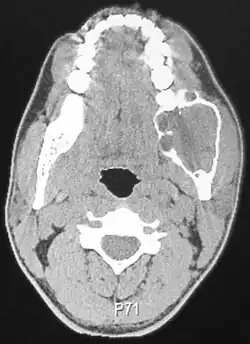

Radiographically, the tumour area appears as a rounded and well-defined lucency in the bone with varying size and features. Numerous cyst-like radiolucent areas can be seen in larger tumours (multi-locular) giving a characteristic "soap bubble" appearance. A single radiolucent area can be seen in smaller tumours (unilocular).[8] The radiodensity of an ameloblastoma is about 30 Hounsfield units, which is about the same as keratocystic odontogenic tumours. However, ameloblastomas show more bone expansion and seldom show high density areas.[15]

Lingual plate expansion is helpful in diagnosing ameloblastoma as cysts rarely do this. Resorption of roots of involved teeth can be seen in some cases, but is not unique to ameloblastoma.[10]